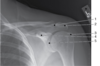

Which letter identifies the costal surface of the scapula?

C - K

The radiograph illustrates an AP projection of the scapula; abduction of the arm moves the scapula away from the rib cage, revealing a greater portion of the scapula than would be visualized with the arm at the side. A number of bony structures are identified: the acromion process (A), the humeral head (B), glenoid fossa (C), scapular spine (D), clavicle (E), supraspinatus fossa (F), acromioclavicular joint (G), scapular notch (H), coracoid process (I), inferior angle/apex (J), body/distal surface (K), lateral/axillary border (L), axillary part upper rib (M